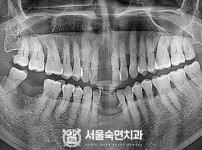

임플란트-전후사진1